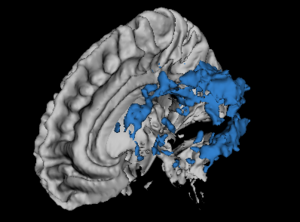

This extension provides image segmentation and local image contrast enhancement approaches in order to detect abnormal white matter voxels signals in magnetic resonance images. At moment, there are available the LS Segmenter (specific for hyperintense Multiple Sclerosis lesion segmentation on T2-FLAIR images), LS Contrast Enhancement (specific to increase the contrast of abnormal voxels of T2-FLAIR images) and AFT Segmenter as a simple implementation of a recent automatic Multiple Sclerosis (MS) lesion segmentation[1] approaches. The LS Segmenter module implements a T2-FLAIR hyperintense lesion segmentation based on the algorithm published in the paper[2].